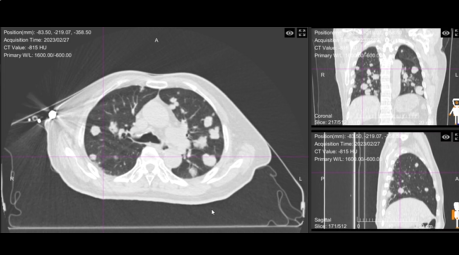

62岁的刘女士就是这项技术的受益者之一。她被确诊为肺继发恶性肿瘤(pT0N0M1 IV期),PET/CT检查显示右肺上叶有混合磨玻璃状密度增高影,代谢增高,考虑为肺转移。在传统治疗方案受限的情况下,这项全新的重离子治疗技术,为她带来了新的康复希望。